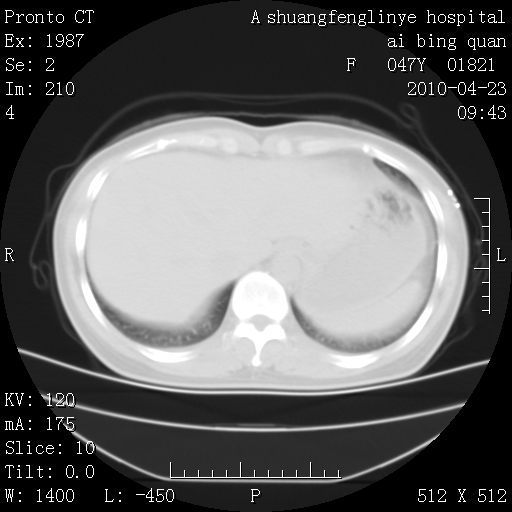

标题: CT25944:胸痛、气短、前几日高烧!肺Ca?请会诊! [打印本页]

标题: CT25944:胸痛、气短、前几日高烧!肺Ca?请会诊!

左侧乳腺低密度灶